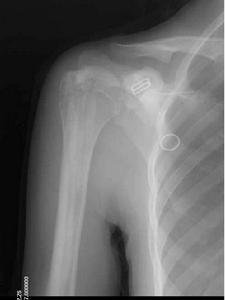

本病突出的x線改變為廣泛性骨硬化,骨呈無結構的密度增高,骨小梁影像消失,可累及全身或大部骨骼。其易發部位為脊柱、骨盆、肋骨、顱骨、脛腓骨及手足的短管狀骨。患者骨密度顯著增加,皮質增厚,髓腔變窄甚至閉塞。病變呈對稱性分布,小兒期即可顯示病變,重者未出生前子宮內即可發現。

(3)顱骨:病變主要在顱底,尤其是蝶骨體及大、小翼改變明顯。蝶鞍大小正常,但鞍底、鞍背及前後床突皆增厚、變硬。枕骨及顳骨亦有明顯硬化。視神經孔變窄且邊緣模糊,乳突氣泡及副鼻竇腔均小或不發育。

X線表現:基本X線表現廣泛均勻,骨密度增高硬化,骨小梁變粗、模糊,皮質增厚,髓腔狹窄,甚至消失。本院曾有3例石骨症病人,因發生骨折,欲行帶鎖髓內針固定,因髓腔消失,骨質硬化,改用鋼板或動力髁鋼板固定,骨密度增高有明顯的均勻對稱性,以四肢、肋骨和骨盆較明顯。骨中骨主要見於掌指、跖趾關節及肋骨等,骨中骨表現為邊界比較明顯的緻密骨島。夾心椎又名夾心蛋糕征,其形成是由於椎體上下軟骨板富含血管,在鈣吸收不足的情況,該部類骨質沉積過多。類骨質對破骨細胞具有明顯的抑制作用,而椎體中部缺乏這種類骨質,故而被破骨細胞侵蝕,形成椎上下高密度而中間低密度,形如三明治樣。髂骨翼年輪樣改變。射線可透過帶是較正常骨區域,而緻密帶存在大量不起作用的破骨細胞。顱骨穹窿顱底均增厚硬化,以顱底骨質增生最明顯。

本病X線表現具有特徵性,其特徵為骨骼濃厚緻密,失去其原有結構,無法區分皮質及髓腔,兩端膨大呈杵狀。有的患嬰在子宮內已有如此表現。全身大多數骨均可累及,但下頜骨少見。由於骨硬化過程可以變緩或暫停,因此,在骨骼上可見到有深淺不同的橫紋。骨骺亦緻密,有時可見呈同心圓狀。椎體的上、下兩端緻密,但中間有一條骨質正常的帶,常被形容為“夾心麵包椎體”。顱骨亦硬化,氣竇消失,垂體窩變淺,鞍背突增生,顱窩變狹,顱孔縮小。

石骨症為全身性骨骼受累的疾病,顱骨的X線表現為硬化,尤以顱底為顯著,特別是蝶骨體及大、小翼均明顯改變。蝶鞍大小正常或縮小,床突、鞍底皆硬化。顳骨及枕骨也可硬化,使板障封閉,失去三層的分野。頂骨額骨及顏面骨可不受侵犯或僅有輕微變化。視神經孔變窄且邊緣模糊乳突小房及鼻旁竇變小或發育不全石骨症在長管狀骨及脊椎有特徵性的X線改變。脊椎椎體表現為上下緣特别致密,其間密度低者為正常骨質,組成三層帶狀影。長管狀骨表現為“骨內骨”,骨質緻密髓腔變窄或消失於乾骺部顯示多條互為平行或呈波狀緻密線紋,乾骺部可呈杵狀變形,尤其脛骨上端內側可表現為邊緣不整呈粗鋸齒改變,髂骨翼典型改變為平行髂嵴,的多層的同心弧狀硬化帶此外,肋骨和鎖骨均可呈均勻硬化。有時還可見到骨折,於掌、蹠、指及趾骨常有界限分明的骨島出現。